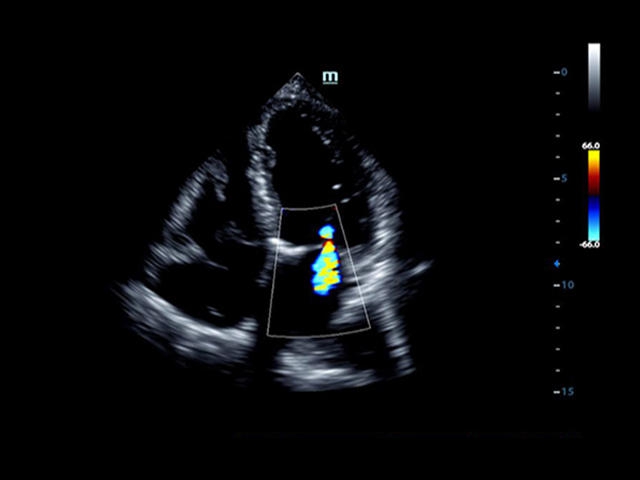

Кардиология:

• LVO - опция проведения исследования левого желудочка с применением контрастных веществ

• Cardiac package - предустановленные параметры, аннотации, маркеры, программы измерений для кардиологии